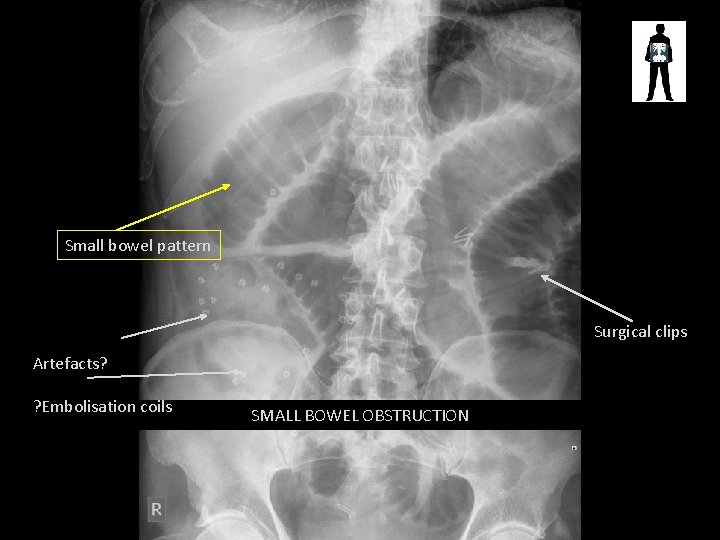

Small bowel pattern Surgical clips Artefacts? ? Embolisation coils SMALL BOWEL OBSTRUCTION

Other SBO signs • “string of pearls” • Small bubbles of air trapped in the valvulae of small bowel